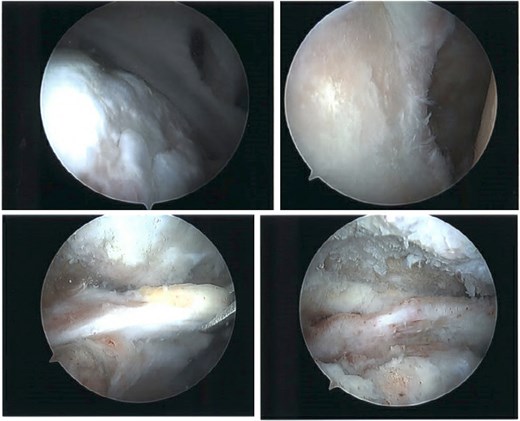

The patient continued to experience right shoulder disability, including pain, limited range of motion, and sleep disturbance. Operative intervention was delayed due to elevated liver enzymes, attributed to chronic acetaminophen use; he underwent right shoulder arthroscopy ~9 months after injury. Intraoperative findings confirmed extensive, irreparable tearing of the supraspinatus and infraspinatus, glenohumeral degenerative change, and deficient biceps tendon (Fig. 8). The joint was debrided and staged reverse total shoulder arthroplasty (rTSA) was discussed.

Intraoperative imaging of right shoulder arthroscopic debridement including findings of full-thickness supraspinatus and subscapularis tendon tears, which subsequently were not able to be repaired, as well as significant glenohumeral degenerative change.